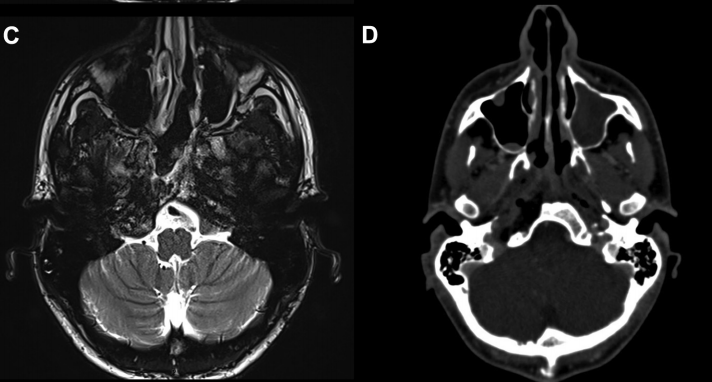

23岁法国小伙Lucas因右侧舌下麻痹和舌萎缩就诊,发现以颈静脉结节为中心的T2高信号和溶骨性病变(图1A和B)。

▼图1.术前MR显示以右颈静脉结节为中心病变,位于颈静脉孔内侧,考虑软骨肉瘤可能。

▼图2,术后MR证实软骨肉瘤完全切除。

▼术后影像学证实了肿瘤全切(图7C)和颈静脉孔保留通畅(图7D)。在这种情况下,神经内镜筷子技术有助于顺利合适地暴露、探查神经和斜坡旁颈内动脉,并通过有限且定制的手术入路向下到达对侧肿瘤所在位置颈静脉孔区域。